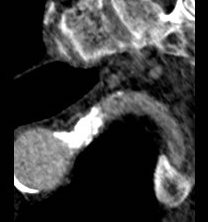

While CT failed to locate this endoleak, abdominal duplex ultrasound did showing flow from a small surface vessel (duplex below, figure at beginning of post). It was not the inferior mesenteric artery which can be treated endovascularly (link) or laparoscopically (link). CT scan suggested that it was one of those anterior branch vessels that one would encounter in exposing the aorta. Usually these were higher up as accessory phrenic arteries, but these fragile vessels, larger than vasovasorum, but smaller than named aortic branches, are seen feeding the tissues of the retroperitoneum.

I waited a year before putting this together as I wanted CT followup. The sac stopped growing and has shrunk a bit back to 5cm or so. There will be those who argue that nothing needed to have been done about this leak as it would have stopped growing eventually, but I would counter that an aneurysm sac that kept growing like the stent graft never went in is one demanding attention. The key role of duplex ultrasound cannot be minimized. We have an excellent team of vascular scientists (their title in Europe), and postop duplex confirmed closure of the leak.